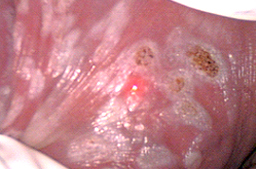

Se ha utilizado la crema 5 Fluoruracilo al 5% (Efudix) la cual teóricamente en esa concentración solo impide la duplicación del DNA viral pero desgraciadamente en el 30% de los pacientes también impide la duplicación del DNA de la piel donde se aplica lo cual ocasiona úlcera (irritación severa y quemaduras que pueden tardar varios meses en sanar), se debe aplicar dos veces por semana durante 12 semanas, tiene una tasa de éxito real del 60%, actualmente solo es usada debido a la ventaja de ser bajo costo ($400.00 pesos el tratamiento completo) pero ocasiona complicaciones con mucha frecuencia, por lo que debe ser aplicada bajo estricta supervisión y responsabilidad del médico tratante, quien determinará si es necesario suspender dicho tratamiento.

Se requiere de 6 a 12 meses de anticoncepción para que el 5 FU sea eliminado del cuerpo ya que puede ocasionar malformaciones congénitas.

Desde hace muchos años se ha observado que si la piel infectada por Virus del Papiloma Humano (piel con lesiones o infectada) es destruida, se regenera con piel sana y el paciente puede eliminar la infección con una tasa de éxito variable dependiendo del tipo de aparato usado, y de la mejora que se obtenga en el sistema inmunológico de cada paciente.

Se han utilizado el electrocauterio y el asa diatérmica para la electrocauterización de las lesiones con una tasa real de éxito muy regular pues existe curación en el 93% de los pacientes, pero el 24% vuelven a presentar las lesiones en menos de 2 años, por lo que la tasa real de éxito es del 69%, y además tienen el inconveniente de ser muy dolorosos ya que no existe un control preciso de la profundidad con la que se destruye la piel por lo que penetran más de 1 mm, y afecta las terminaciones nerviosas, debido a esto los pacientes presentan dolor en los genitales externos, (las mujeres en vulva y los varones en pene) cuando practican deportes que ocasionan fricción en la zona o cuando tienen relaciones sexuales y esto puede durar hasta varios meses. Debido a las secuelas actualmente no se recomiendan dichos procedimientos para tratar los siguientes órganos: vagina, vulva, periné, región peri anal, ano y pene, con lesiones extensas.